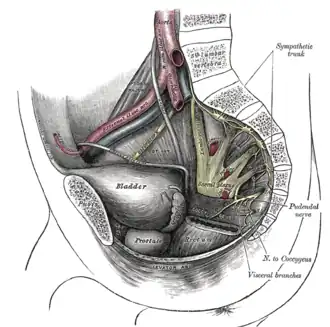

Dissection of side wall of pelvis showing sacral and pudendal plexuses.

Dissection of side wall of pelvis showing sacral and pudendal plexuses. -